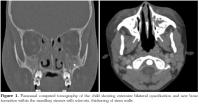

For further evaluation, paranasal CT was performed. The CT showed extensive bilateral opacifications and new bone formation within the maxillary sinuses, with sclerosis, thickening of sinus walls. There was an increased soft tissue thickening and reticulation within the periorbital, peri-zygomatic and premaxillary soft tissues consistent with edema and inflammation. The findings were thought to represent an aggressive and chronic inflammation such as chronic osteomyelitis (Figure 1). Until paranasal infection was ruled out, ampicillin/sulbactam and amikacin therapy were given.

Simmons et al.[10] using CT found that patients with sinonasal involvement have bilateral sinus opacification, concomitant orbital mass, bone erosion, septal perforation, and mucosal inflammation. Maxillary sinus involvement is mostly seen.[11,12] In our case, the CT findings were similar to those of Simmons et al.[10]